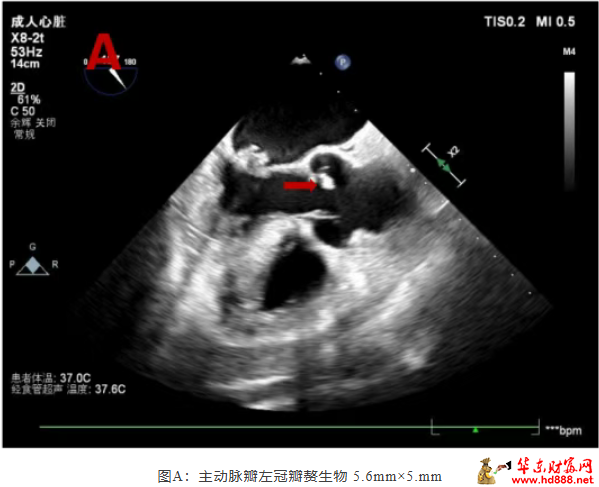

术中所见触目惊心:二尖瓣前叶可见大小约 10mm×5mm 赘生物,后叶腱索断裂并穿孔;主动脉瓣无冠窦可见 5.6mm×5mm 赘生物,左冠瓣亦多处穿孔,心脏瓣膜结构被严重破坏,与术前经食道超声探查结果高度一致!

条带状高回声 13mm×4mm